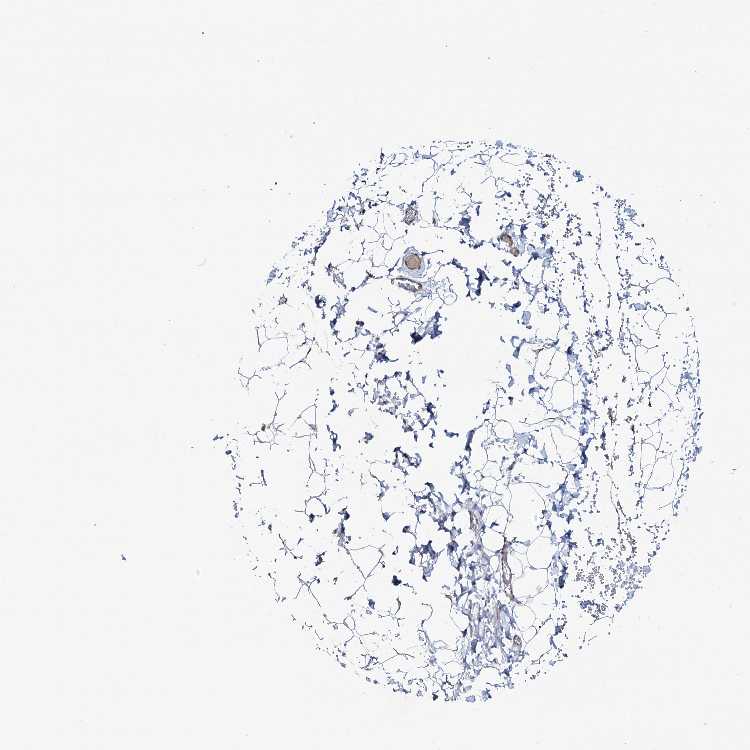

ADIPOSE TISSUE - Antibody stainingi

Antibody staining in the annotated cell types in the current human tissue is reported as not detected, low, medium, or high, based on conventional immunohistochemistry profiling in selected tissues. This score is based on the combination of the staining intensity and fraction of stained cells.

Each image is clickable and will lead to virtual microscopy that enables deeper exploration of all samples and also displays staining intensity scores, fraction scores and subcellular localization as well as patient and tissue information for each sample.

Antibody HPA040410Antibody HPA040441

Adipocytes Not detectedNot detected